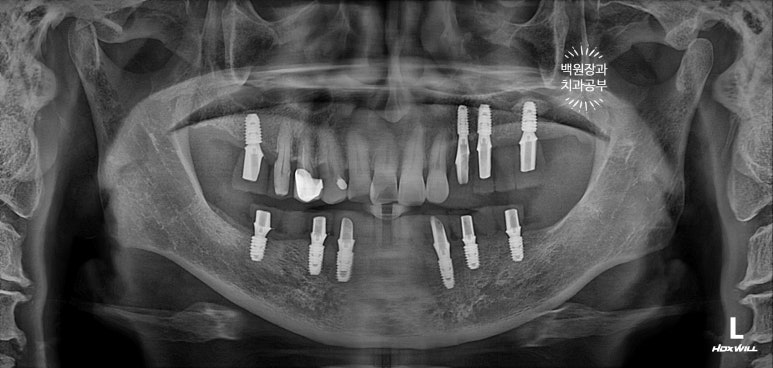

치료가 마무리된 후의 치과용 파노라마 사진입니다.

정~~~말 깔끔하게 마무리가 잘 되었네요!!!

Before & After

치료 전 후 비교로 가장 명확히 볼 수 있는 사진이 치과용 파노라마 사진입니다.

엑스레이에서 보이진 않지만, 아래턱 전체틀니는 이제 사용하지 않아도 되시게 되었고,

만성 치주염으로 흔들리던 위턱의 임플란트들도 깔끔하게 임플란트로 대체되었습니다.